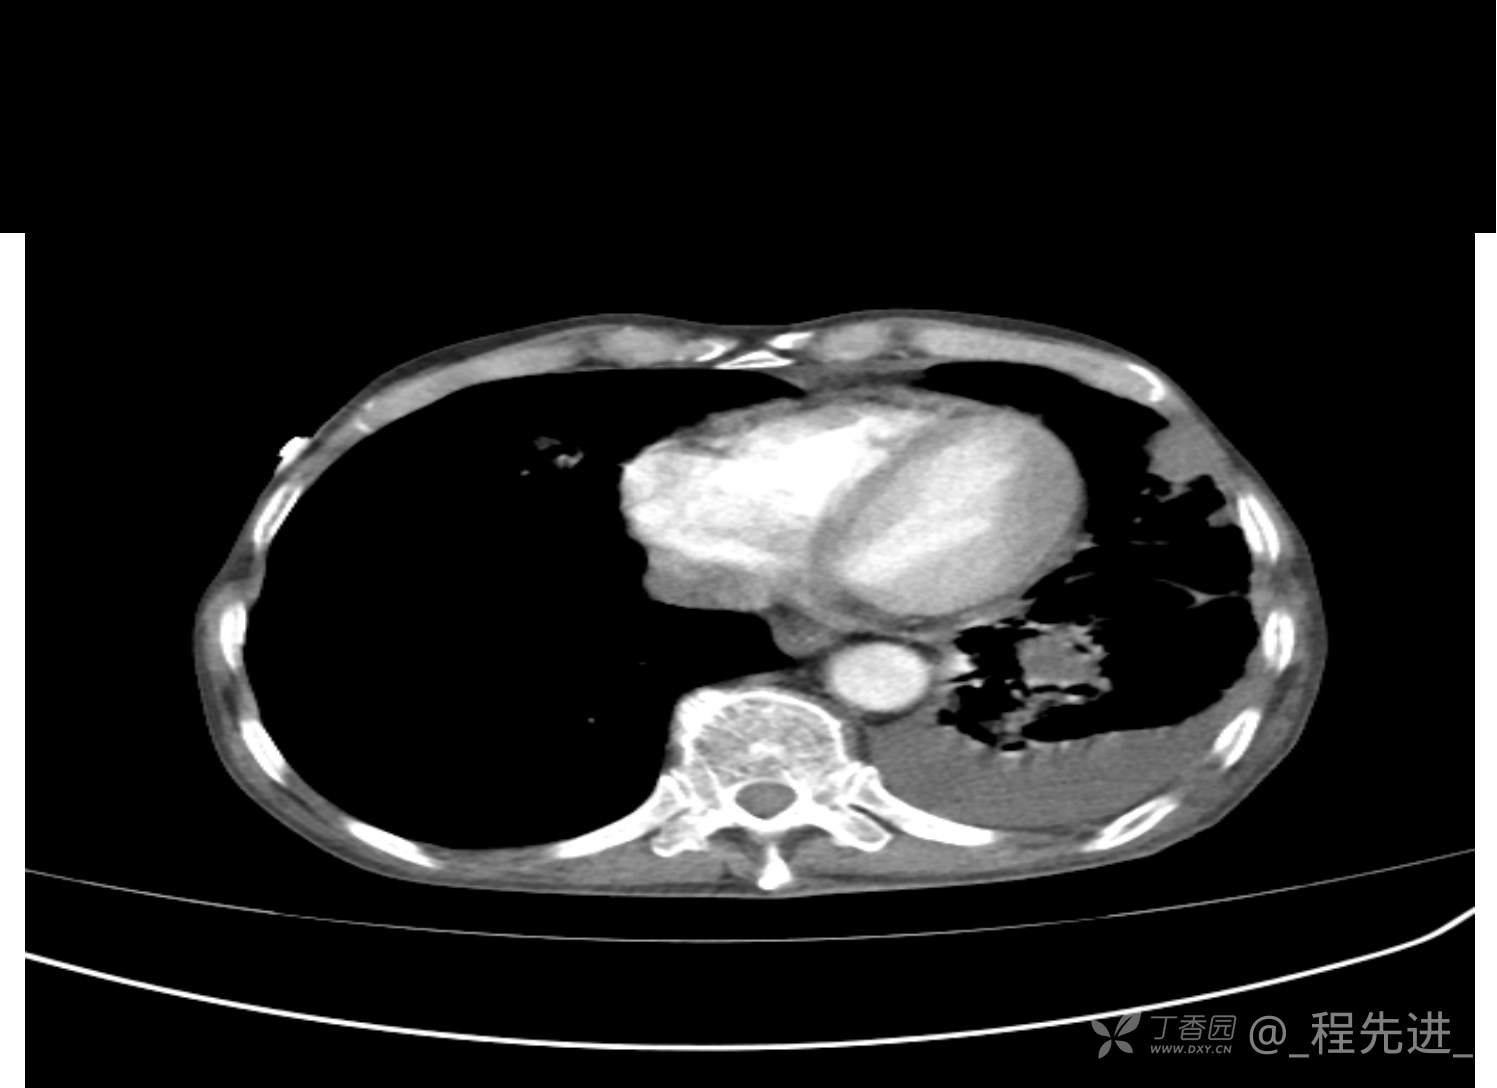

患者性别:男

患者年龄:81岁

简要病史:反复咳嗽、咳痰20余年,加重1周。两肺呼吸音低,可闻及散在干湿啰音。